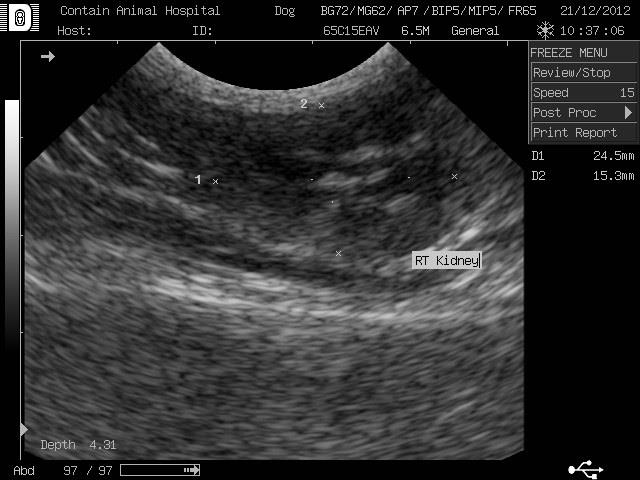

有脫水+肺炎+失溫,進一步檢驗還發現已經腎衰竭(右腎已呈現萎縮)+敗血症。每天給予靜脈點滴.噴霧治療.點眼藥膏!